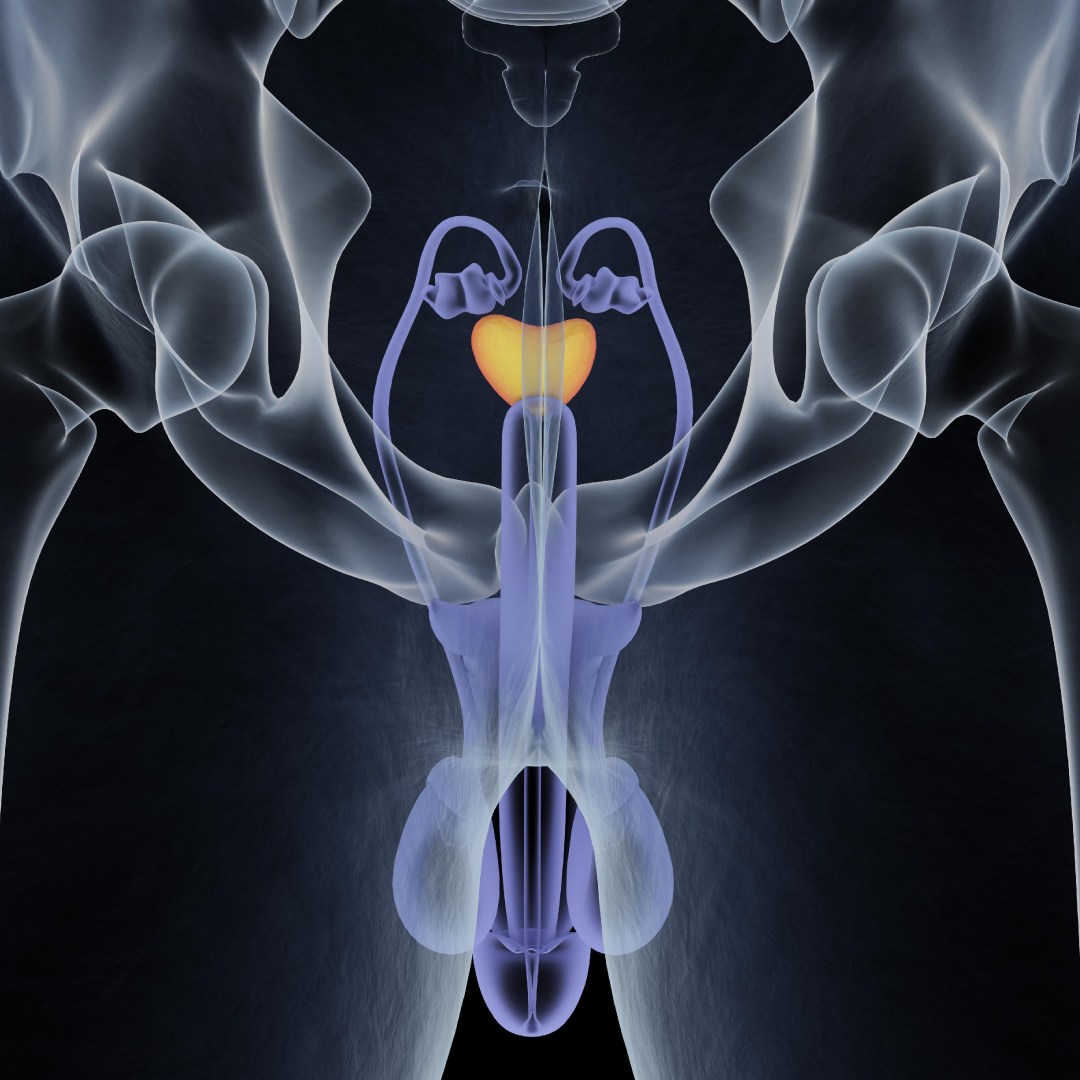

A urologia geral está envolvida na prevenção urológica, rastreio do câncer de próstata, tratamento de infecções sexualmente transmissíveis (ISTs) e problemas urológicos em geral.

É a subespecialidade que lida com o diagnóstico e tratamento dos tumores (benignos e malignos) dos órgãos do trato urinário (rins, ureter, bexiga) e genital masculino (próstata, testículos e pênis).

A próstata é um dos principais órgãos do sistema urinário e reprodutor masculino, pode ser acometida por crescimento benigno, câncer, inflamações, dentre outras patologias. Os homens a partir dos 45 anos devem procurar o urologista preventivamente.

A cirurgia de transplante renal é realizada pelo urologista, com acompanhamento pré e pós-operatório de equipe multidisciplinar liderada pelo médico nefrologista.